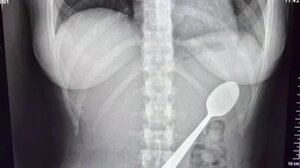

Απίστευτο ατύχημα στο Βέλγιο: 28χρονη κατάπιε κουτάλι 17 εκατοστών όταν πήδηξε πάνω της ο σκύλος της ΚΟΣΜΟΣ 09.02.2026 - 22:05Απίστευτο ατύχημα στο Βέλγιο: 28χρονη κατάπιε κουτάλι 17 εκατοστών όταν πήδηξε πάνω της ο σκύλος της